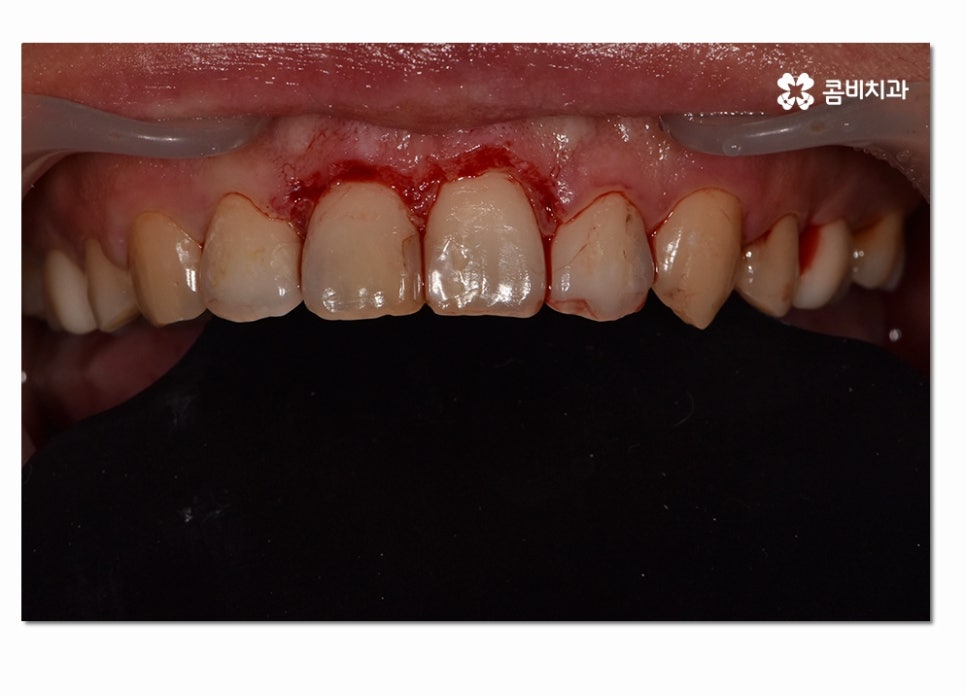

수술적인 치료 방법은 치은절제술과 치은성형술,치주판막술,치주성형술 등을

예로 들 수 있으며 오늘 소개 드리고자 하는 케이스는

치은절제술에 해당하는 치료 방법으로 너무 늦지 않게 치료하여

잇몸과 치아를 건강하게 살린 케이스라고 말씀드릴 수 있어요.

이러한 수술적인 방법은 잇몸을 절개하고 치은 깊숙하게 숨어 있는

치석을 제거해 주거나 치주조직이 다시 건강하게

회복될 수 있도록 형태를 바꿔주며 재생을 돕는 방법이라 할 수 있는데요.